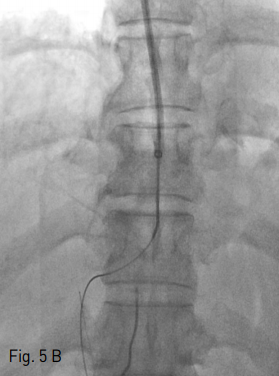

Fig 1A

Contrast enhanced CT scan showed features of chronic liver disease. Axial (A) and coronal (B) images showed hypertrophy of caudate lobe and lateral segments of left lobe with concomitant severe atrophy of the right lobe.

Fig 1B

외부병원에서 시행한 컴퓨터 단층촬영(CT)검사에서, 간의 우엽은 심하게 위축되어 있었고 좌측외엽 및 미상엽은 증대되어 있어 만성간염에 합당한 소견이었다(Fig. 1). 이로 인하여 우측 간문맥 역시 매우 위축되어 있었으며, 우간정맥과 우측 간문맥의 거리가 멀어보였다.